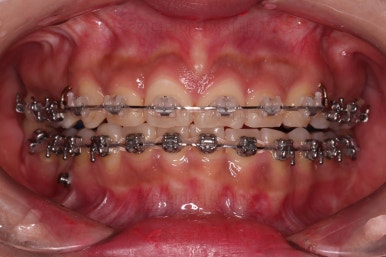

장치를 부착했고요.

이번에 환자분이 선택한 장치는 윗니는 자가결찰 세라믹, 아랫니는 자가결찰 메탈이었습니다.

이렇게 혼용해서 사용해도 되는 조합들이 있고요.

이번 환자분은 웃을 때 이가 많이 보이는 타입이 아니셔서 아랫니는 좀 더 튼튼하고 저렴하기까지한 메탈장치를 선택하셨죠.